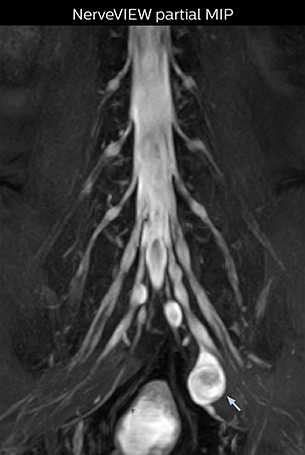

“In such case, we would then browse through axial T2-weighted MR images slice by slice and mentally reconstruct the actual situation based on both radiculography and MRI. Fortunately, NerveVIEW can now very well show nerve courses and presence of nerve compression or edema in one single image series.” “We have often seen NerveVIEW directly depict details of the nerve compression that were not observed by radiculography. Therefore, we think that with NerveVIEW we can reduce the number of invasive examinations, especially for some patients with lumbar plexus symptoms.”

“Before NerveVIEW, diagnosis by MRI alone was sometimes difficult, unless there was a strong suspicion based on clinical symptoms,” says Shoji Yabuki, MD, DMSc, Orthopedic surgeon at Fukushima Medical University School of Medicine. “This is why we routinely perform selective lumbosacral radiculography (nerve root block) and x-ray in such cases. However, radiculography can only depict nerves as far as the contrast agent reaches. When a nerve is distorted by compression, the contrast agent will not pass through this compressed area, preventing us from evaluating the full nerve compression.”

The key concept in MR neurography, Dr. Yabuki stresses, is the ability to directly visualize spinal nerves, versus inferring the presence of pathology indirectly. “Before NerveVIEW, we estimated compression of the nerve by looking for the presence or absence of fat signal on other MR images,” he says.

“For example, in sagittal images, when the presence of fat is observed in the intervertebral foramen, it suggests that there is a margin around the nerve. Similarly, the absence of fat indicates that the nerve is being compressed. So, we used to deduce nerve compression indirectly. With NerveVIEW, however, we can observe the condition of the nerves directly, regardless of the presence or absence of fat. We always prefer such direct observation of anatomy over having to make an inference about it.”